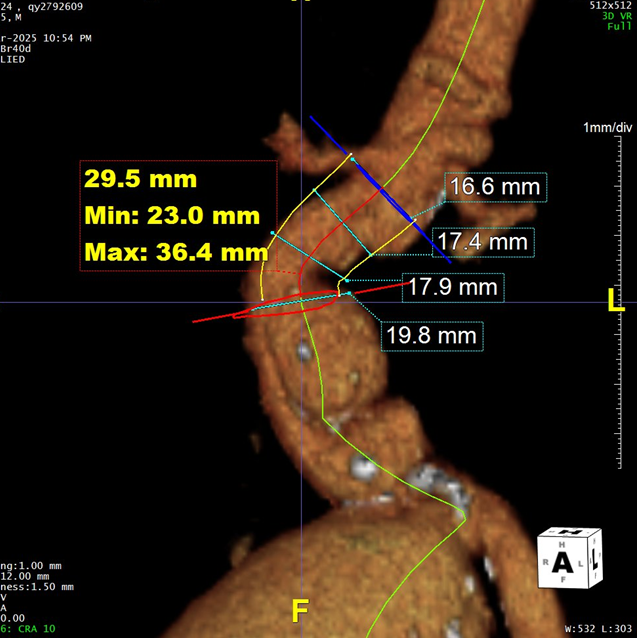

二、术前CTA详解

结合近远端血管直径及锚定区长度选择:戈尔C3支架主体 RLT231412 ;双侧接髂支,左侧覆盖至髂总远端,保留左侧髂内;右侧覆盖至髂外动脉,配合使用弹簧圈对巨大瘤腔进行填塞。